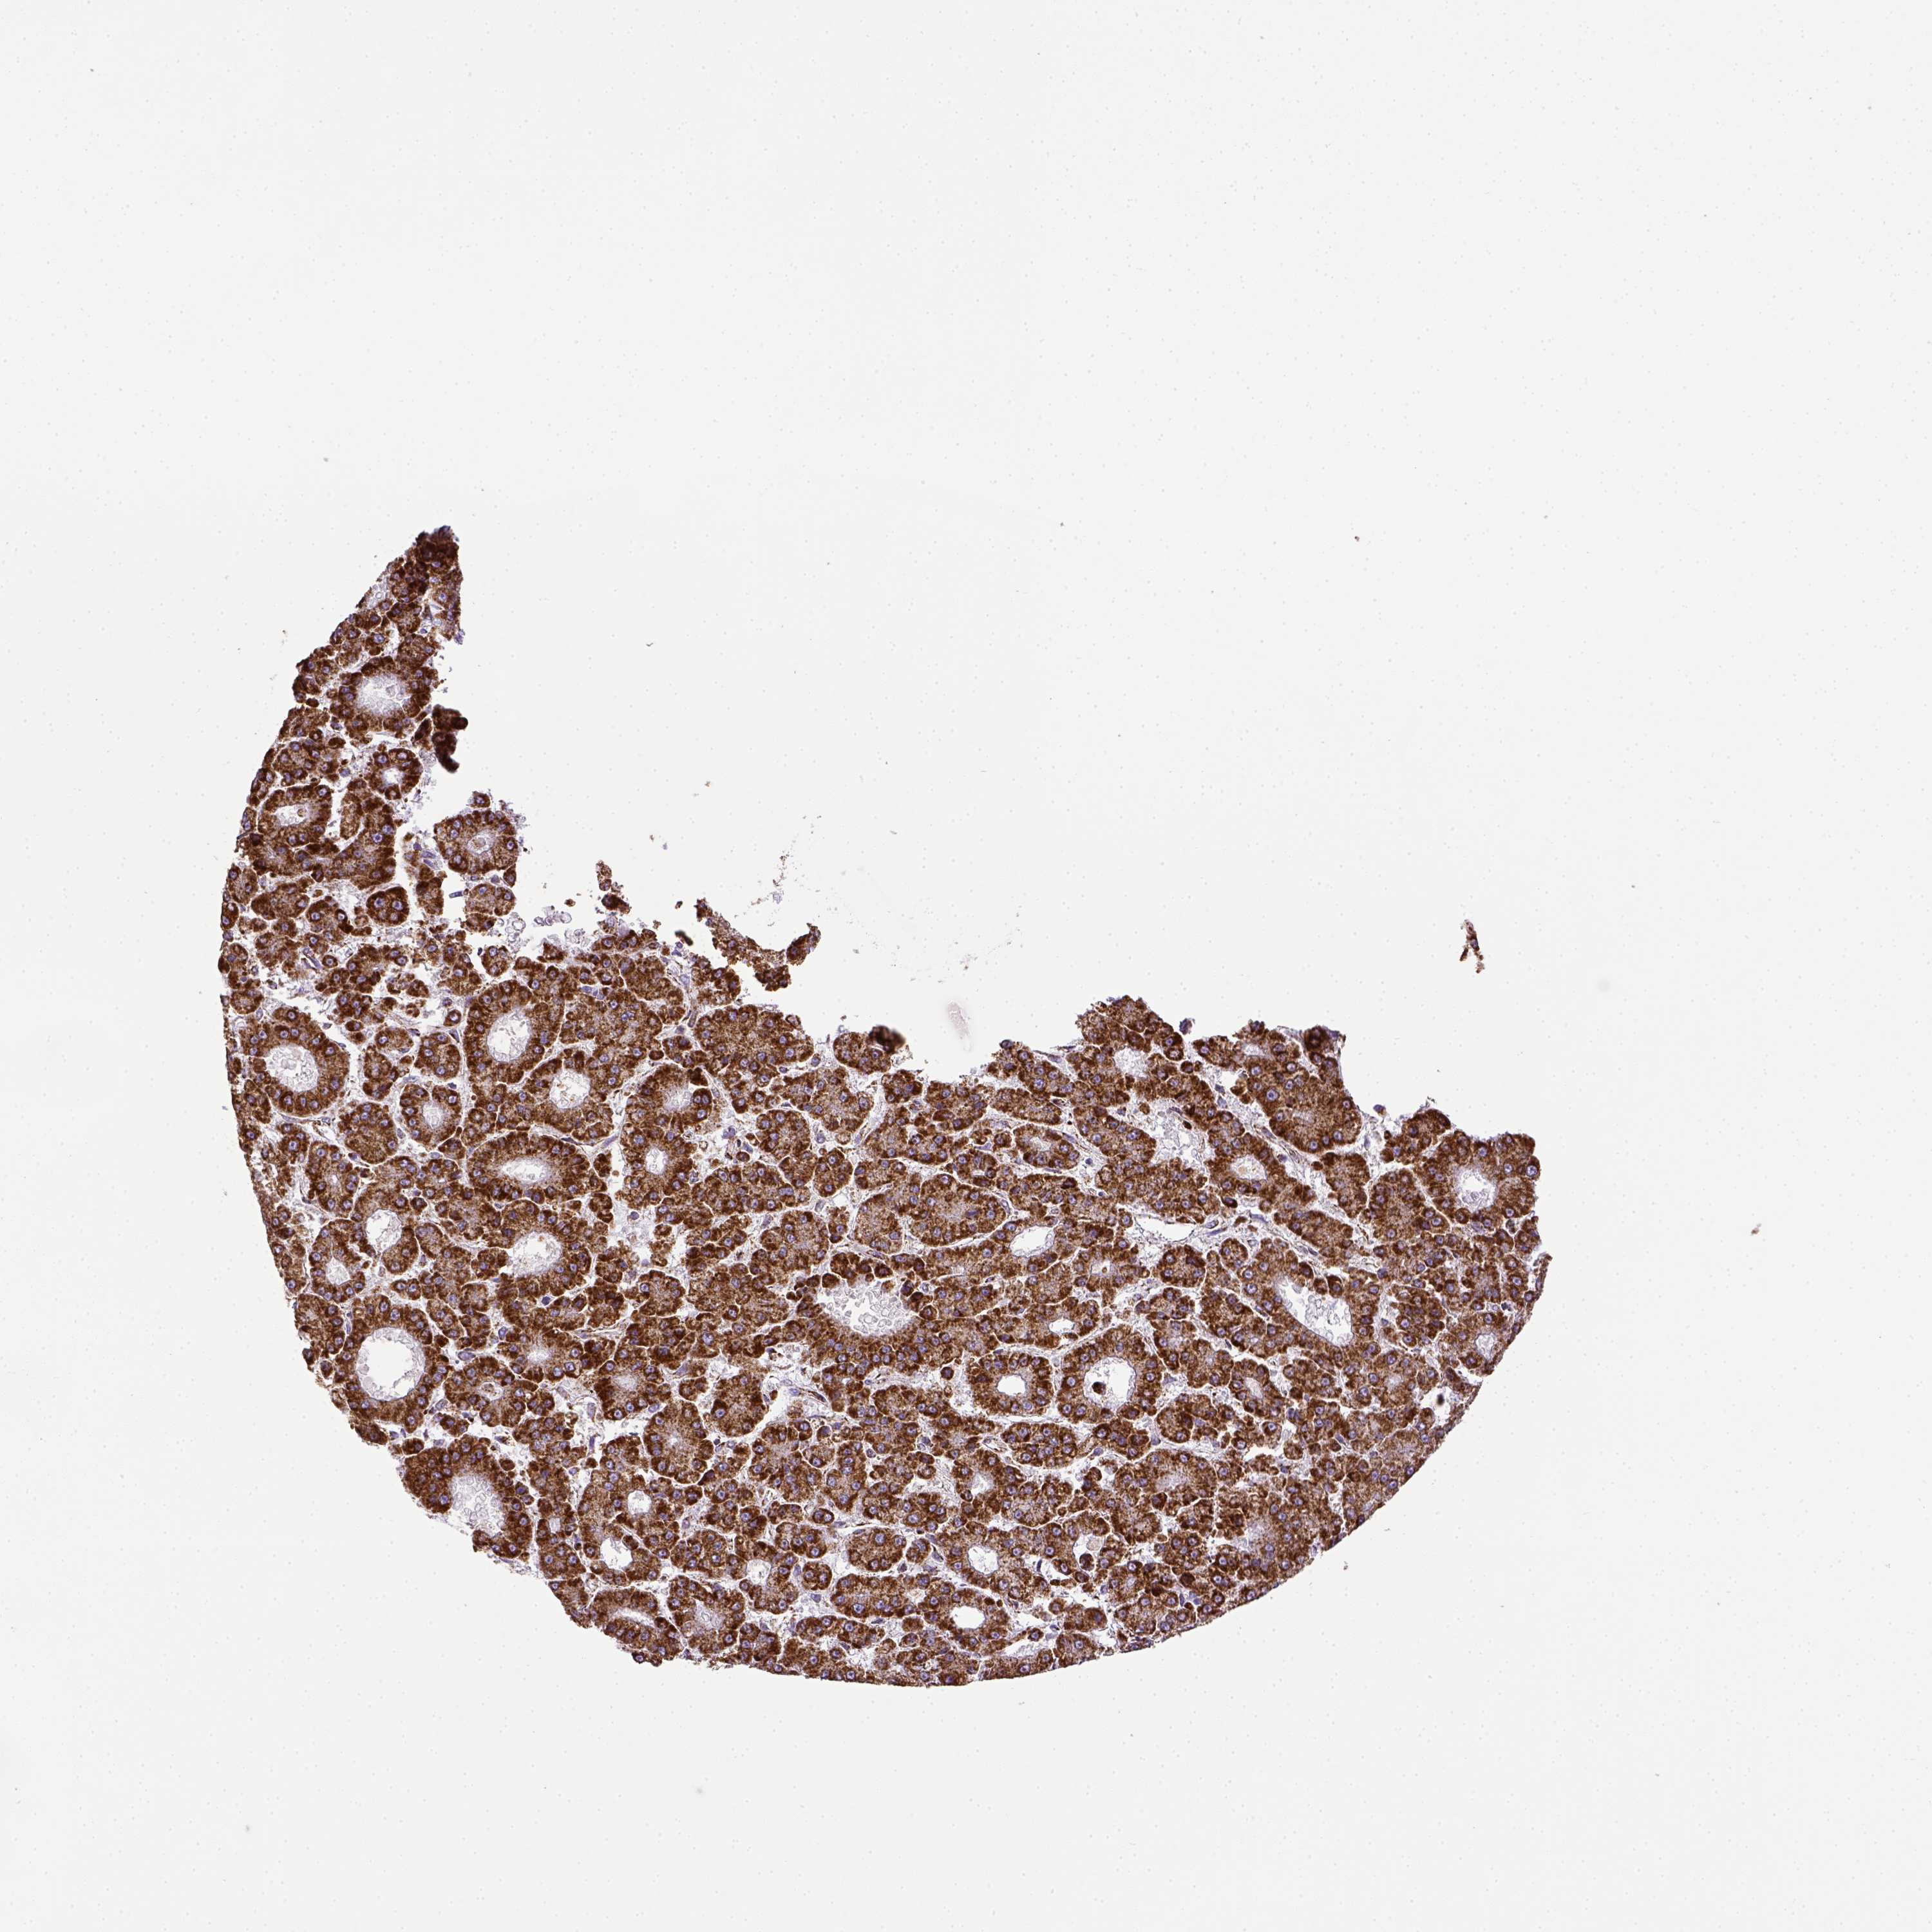

LIVER CANCER - Protein expressioni

A mouse-over function shows sample information and annotation data. Click on an image to view it in a full screen mode. Samples can be filtered based on level of antibody staining by selecting one or several of the following categories: high, medium, low and not detected. The assay and annotation is described here.

Note that samples used for immunohistochemistry by the Human Protein Atlas do not correspond to samples in the TCGA dataset.

Antibody stainingi

Antibody staining in the annotated cell types in the current human tissue is reported as not detected, low, medium, or high, based on conventional immunohistochemistry profiling in selected tissues. This score is based on the combination of the staining intensity and fraction of stained cells.

Each image is clickable and will lead to virtual microscopy that enables deeper exploration of all samples and also displays staining intensity scores, fraction scores and subcellular localization as well as patient and tissue information for each sample.

Antibody HPA069328

Antibody CAB016241

Staining

High

Medium

Low

Not detected

Intensity

Strong

Moderate

Weak

Negative

Quantity

>75%

75%-25%

<25%

None

Location

Nuclear

Cytoplasmic/membranous

Cytoplasmic/membranous,nuclear

Carcinoma, Hepatocellular, NOS

Cholangiocarcinoma